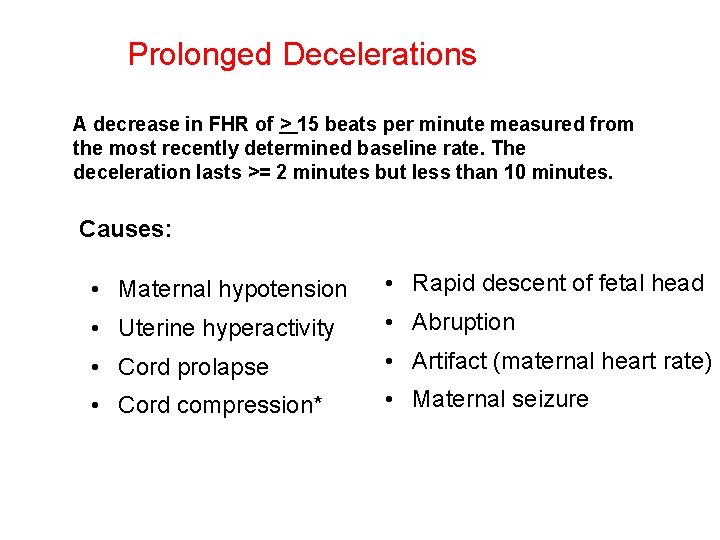

Prolonged Decelerations A decrease in FHR of > 15 beats per minute measured from the most recently determined baseline rate. The deceleration lasts >= 2 minutes but less than 10 minutes. Causes: • Maternal hypotension • Rapid descent of fetal head • Uterine hyperactivity • Abruption • Cord prolapse • Artifact (maternal heart rate) • Cord compression* • Maternal seizure